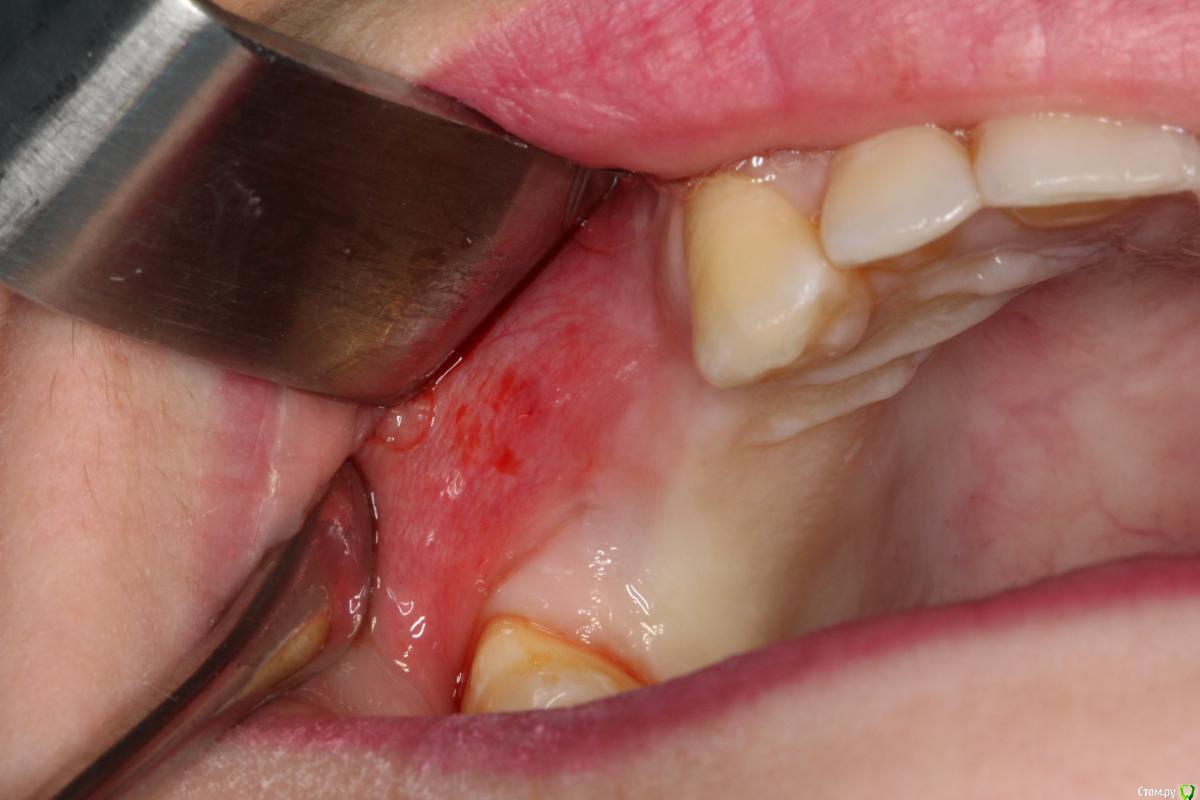

Robinbobin Опубликовано 25 марта, 2015 Поделиться Опубликовано 25 марта, 2015 Имплантаты Dio UF ll,костный материал ауто+остеоматрикс.Хотелось бы услышать мои ошибки 6 Ссылка на комментарий

red_butler Опубликовано 25 марта, 2015 Поделиться Опубликовано 25 марта, 2015 я бы обошелся без вертикального разреза, и делал бы разрез по гребню. Почему делали открытый синус? Ссылка на комментарий

Robinbobin Опубликовано 25 марта, 2015 Автор Поделиться Опубликовано 25 марта, 2015 я бы обошелся без вертикального разреза, и делал бы разрез по гребню. Почему делали открытый синус? Я делал разрез по гребню но из-за маленького опыта порвал((((Делал открытый потому что объем кости был 2-2.5 мм а боком поставить побоялся) Ссылка на комментарий

DShu Опубликовано 28 марта, 2015 Поделиться Опубликовано 28 марта, 2015 Вертикальный разрез лучше один, по дистальной п-ти 17го. А так норм. Ссылка на комментарий